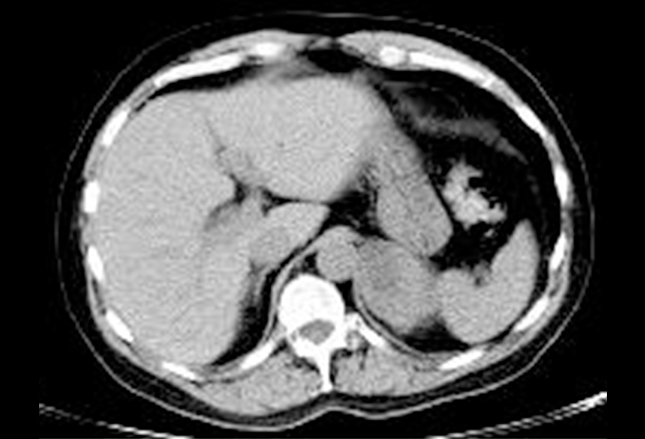

肾上腺也是SCLC扩散的常见部位。上图为腹部肾上腺处非增强CT扫描,可见大的低密度左肾上腺组织。对于SCLC患者,这种情况很可能是疾病转移的表现。